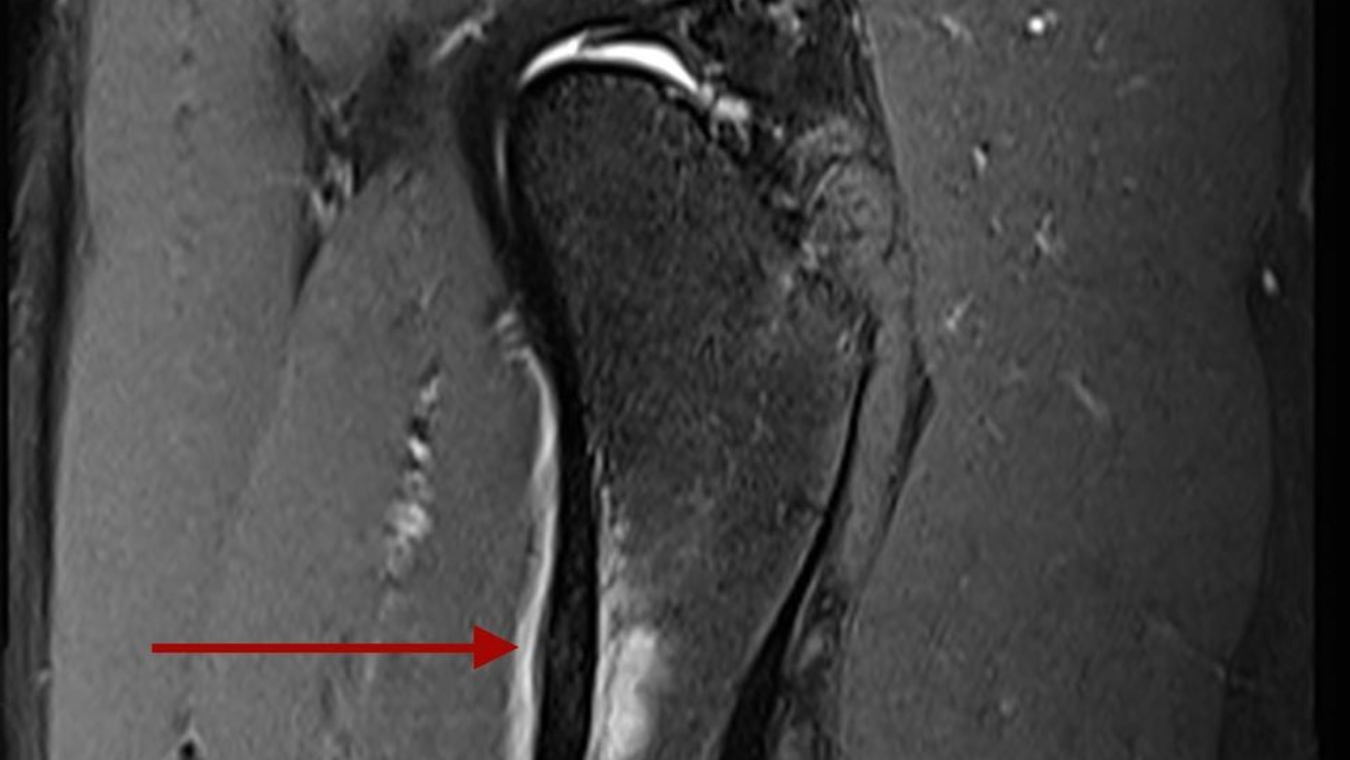

Fractura por estrés en el fémur de Alistair Brownlee.

“El annus horribilis continúa. Lamentablemente, tengo una fractura por estrés en el fémur y no correré el resto del año. Los últimos meses han sido más que una pequeña prueba“, ha escrito el británico en sus redes sociales.